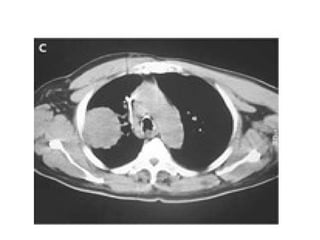

83 years old lady chronic AF , Dysphagia

An esophagogram obtained to evaluate dysphagia for solid food revealed a prominent impression of the left atrium on the esophagus , without evidence of obstruction.

Chest radiography (Panel A) revealed cardiomegaly (cardiothoracic ratio, 0.86), splaying of the carina, and an elevated left main bronchus (arrows). Plus PPM DDD

Echocardiogram showed massive biatrial enlargement (left larger than right),

An 83-year-old woman with long-standing atrial fibrillation who had previously undergone atrioventricular nodal ablation and pacemaker placement presented with symptoms of progressive heart failure. The patient was discharged home on medical management after prolonged diuresis.